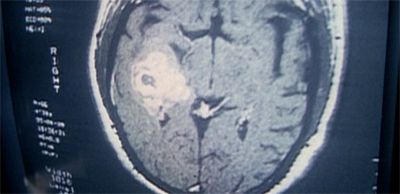

The brains of the operation...

The brains of the operation…

In hindsight, Pusher seems like a very important episode for Vince Gilligan. It is the story of a nobody with above-average intelligence who finds himself confronted with his own mortality. Using the remainder of his time on Earth, the character works hard to make himself feel important and powerful – to account for his own shortcomings and inadequacies. He becomes so addicted to this thrill that he risks his life repeatedly in pursuit of it.

At the end of the episode, Mulder paraphrases a statement that Scully made earlier on.“He was always such a… little man,” Mulder reflects. “This was finally something that made him feel big.” The character is unable to give that up, despite the danger involved, and the damage that it causes to other people around him. It is very hard not to see a little of Walter White in Robert Patrick Modell, a man finally cracking under the pressure and attempting to construct a grand mythology around himself.

The brain is the strongest muscle.

Similarly, his work on Breaking Bad is a lot tighter and more densely woven than the majority of his work on The X-Files. Excluding the rather meticulously constructed and interwoven Bad Blood, Gilligan’s episodes tended to feel a little bit hazy around the edges. For example, Pusher is rather vague about the specifics of what Robert Patrick Modell can do, and how exactly he does it – to the point where the audience might be left scratching their heads.

For example, Mulder states that “his voice seems to be the key”, but he is able to infiltrate the FBI with a piece of paper with the word “Pass” written on it. How does he get from “cerulean is a gentle breeze” to “please crash the car”? How come he can’t control Skinner? Is it because he is exhausted, or just because Skinner is that much of a badass? There is something just a little bit hazy about how exactly Modell does what he does.